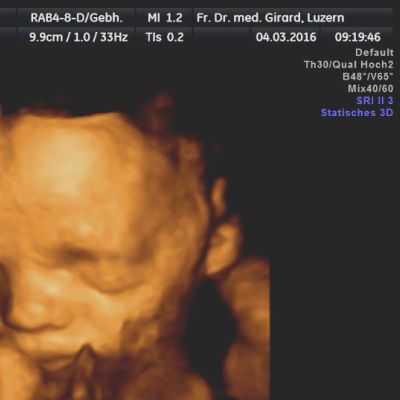

Der Ultraschall hilft uns dabei als einzige Methode, das ungeborene Kind in der Gebärmutter direkt sichtbar zu machen.

können das Wachstum des Kindes und die Fruchtwasser-Menge, wichtige Hinweise auf eine normale Entwicklung des Kindes, beurteilt werden. In diesem Alter können auch schwerere Fehlbildungen erfasst werden, beispielsweise von Kopf und Gehirn, Wirbelsäule, Herz, Nieren, Magen und Extremitäten. Ebenso wird der Sitz der Plazenta beurteilt.

steht das kindliche Wachstum im Vordergrund. Ein normal grosses Kind und eine normale Fruchtwasser-Menge sprechen für eine normale Funktion der Plazenta. Auch die Lage des Kindes in der Gebärmutter gewinnt zunehmend an Bedeutung, sollte sich das Kind doch gegen den Geburts-Termin in eine Schädellage drehen. Zudem können einige Fehlbildungen des Kindes, die für die optimale Betreuung des Kindes nach der Geburt von Bedeutung sein können, erst in diesem späten Schwangerschafts-Alter erfasst werden.